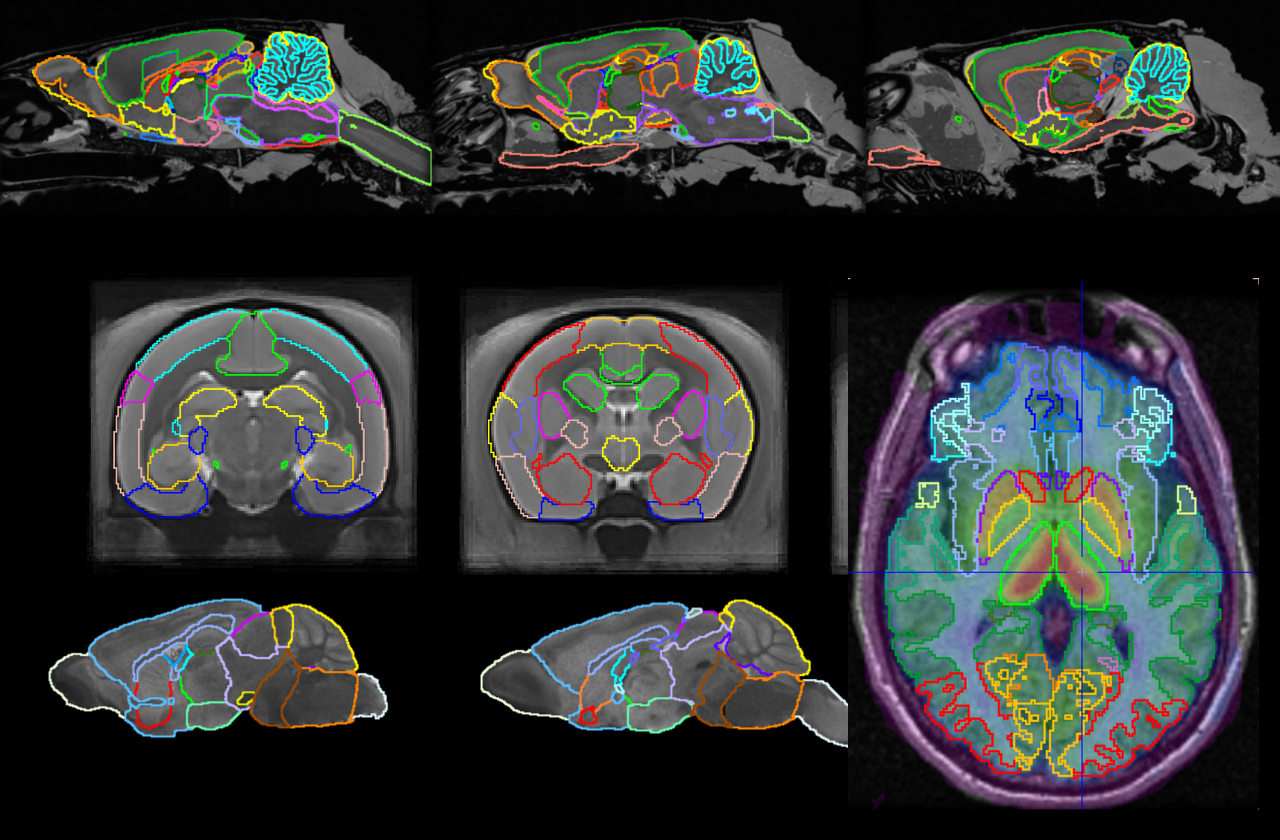

Workflow-based brain segmentation helps you extract the statistics you need for PET and PET/MR. User-expandable brain atlas resources help you customise for your research.

PNEURO Human Brain Analysis & Neurology Package

pmod’s PNEURO tool gives you streamlined segmentation for human brain PET and PET/MR and direct access to statistics, kinetic modelling & parametric mapping.

PNROD Rodent Brain Analysis

PNROD gives you brain segmentation workflows for small animal PET, PET/CT and PET/MR with the same direct access to statistics, kinetic modelling & parametric mapping.